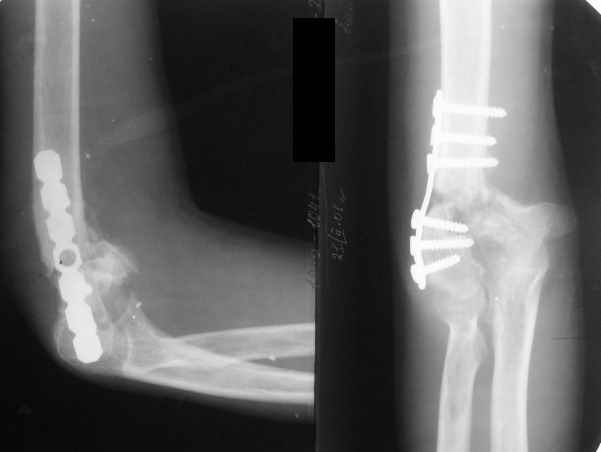

The recent x rays show established Non union with poor quality bone in the distal fragement. The joint is also appearing degenerate. In view of the multiple failed reconstructive surgeries, an Elbow replacement would seem reasonable.

However it would have to be a fully constrained one as there would be missing bone stock.

Уважаемый Ильдар, в ноябре 2005 г. мы оперировали практически полностью идентичную ситуацию у больного с гемофилией, поставили модифицированный

эндопротез локтевого сустава типа Сиваша с хорошим результатом. На заводе-производителе (в нашем случае - завод ЦИТО, но есть еще ООО

Эндосервис т/ф (095) 221-06-18, 500-41-30, 513-54-32 ) можно заказать протез этого типа по индивидуальным размерам для восполнения дефицита длины плечевой кости. Сейчас есть и более дорогие коммерческие эндопротезы фирмы Stryker. Наиболее активно оперируют локоть в ЦИТО, у нас тоже есть